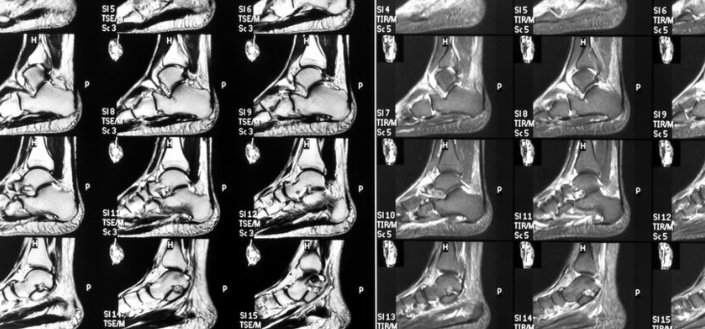

Pruebas de imagen: ecografía o resonancia magnética para confirmar la inflamación del nervio y descartar otras lesiones.